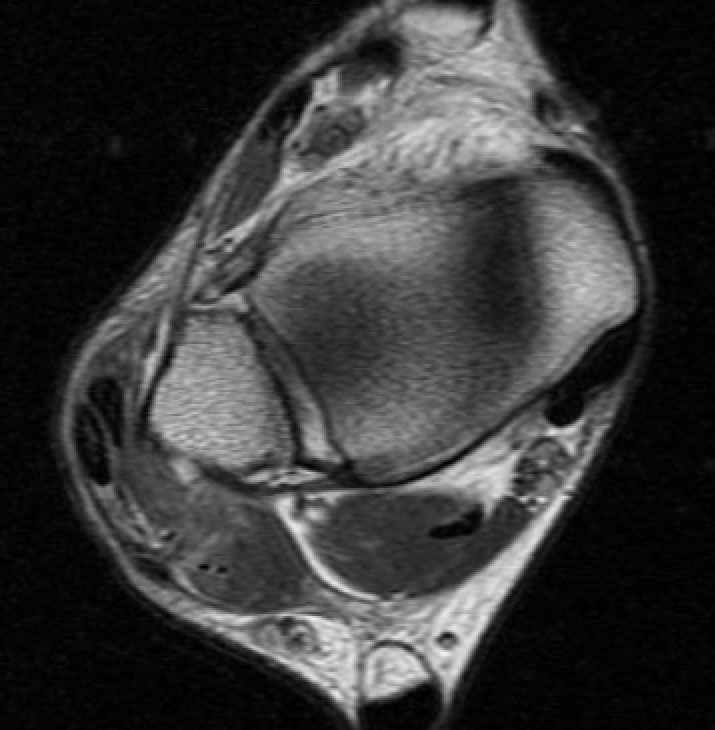

MRI

Anterior subluxation of peroneal tendons

Anterior subluxation of peroneal tendons